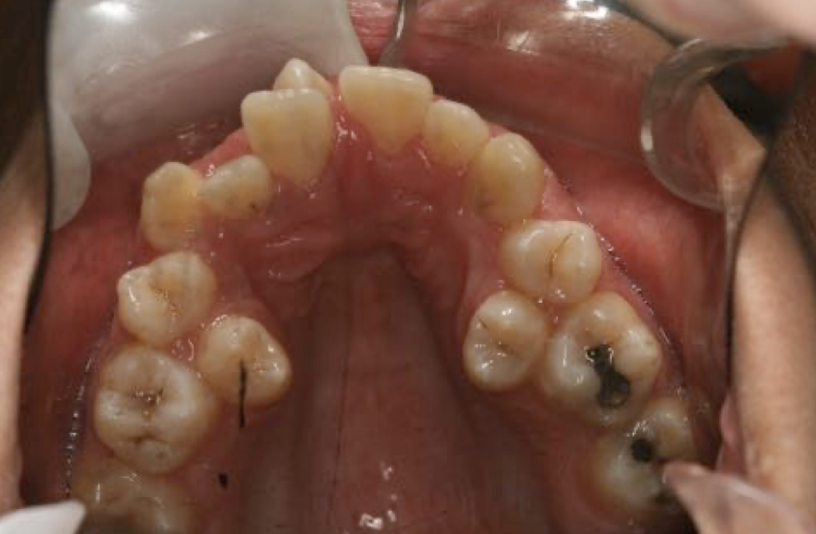

What dental anomaly is this?

Taurodontism